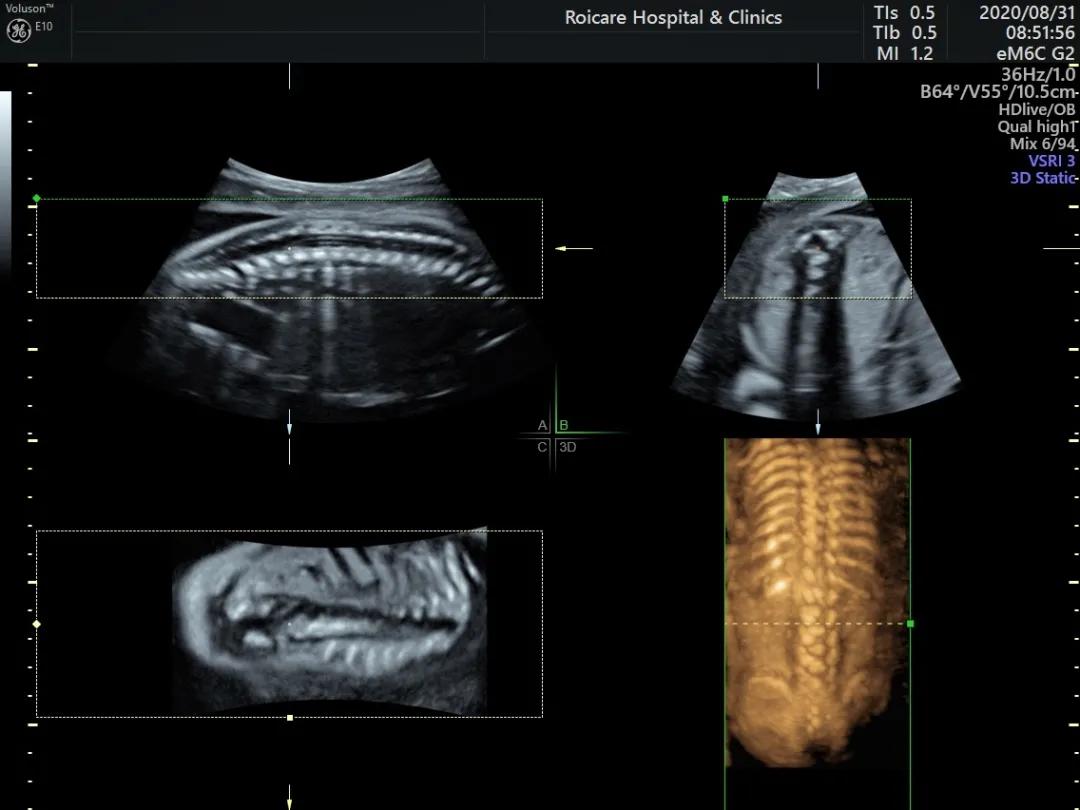

脊髓圆锥低位

脊柱裂

正常孕20周以上的胎儿脊髓圆锥的位置达到L3水平以上,如果孕20周以上胎儿脊髓圆锥位置在L4以下,要警惕脊柱裂可能以及是否合并其他异常。中孕期产前超声检查可以发现严重的开放脊柱裂。闭合性脊柱裂表现多样、脊柱裂口小、影像学表现不典型,因此产前超声诊断困难。